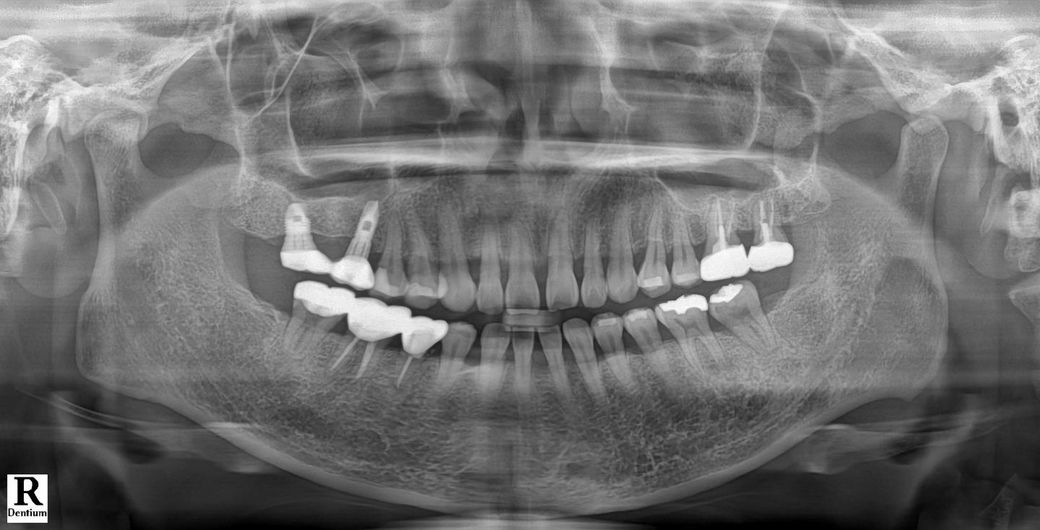

엑스레이좀 봐주세요! 치아가 아파요

엑스레이상 왼쪽 아래부분이 뜨거운걸 먹었을때

애리는 느낌이 나요.

이미 신경치료15회와 + 다른이 신경치료+ 크라운 한 세곳중 한곳이 아픈듯해요.

병원 3군데선 염증 안보인다하고 한곳은 왼쪽 아래 소구치에서 약간 염증이 보이나 신경치료 완료한지 아직 2달밖에 안된거라 지켜봐야 한다고 하더라구요..

그러면서 ...왼쪽 윗부분 인레이도 뭔가 애메하다는듯이 말을 흐리셨는데 충치나 염증이 보이나요~?

• 2번 째 사진

엑스레이 상으로 보면 신경치료는 잘된거 같습니다. 차가운거나 뜨거운거에 반응이 잇다면 다른 치아가 아닐까 생각되기도 합니다.

1. 신경치료된 치아는 보통 찬 것에는 거의 증상이 없고 간혹 염증이 아직 있거나, 잔존신경이 있으면 뜨거운 것에 민감한 반응을 보이기도 합니다.

3. 현재로서는 신경치료를 안하고 씌운 마지막 큰 어금니에 대해 추가검사를 해보면 좋을 것 같습니다.

4. 엑스레이상 왼쪽 위 작은 어금니 인레이 (#15)의 경우 인레이 보철물 하방 검은 색이 하방 우식일 수도 있고 엑스레이 상 왜곡일 수도 있습니다. 증상이 있다면 인레이 뜯고 내부 체크해봐야 합니다.